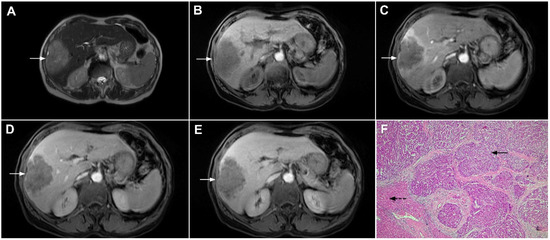

Mucinous cholangiocarcinoma is a rare variant of mICC characterized by rich mucin production [24,27]. According to previous studies, mucinous mICC originate from mucin-producing cholangiocytes located in large bile ducts [28]. Imaging findings in mucinous mICC reflect characteristic histopathological features of the lesion with cancer cell nests suspended in a large mucinous lake [29]. Therefore, these lesions display strong T2-weighted hyperintensity [27]. Moreover, as cancer cells in the center of the lesion are scarce, these tumors show only slight progressive enhancement of intralesional septa and cellular nests in postcontrast studies (Figure 7) [27]. Due to its very high signal intensity on T2-weighted images and centripetal pattern of enhancement, mucinous mICC may be misdiagnosed as hemangiomas [29]. Concerning similarities in the postcontrast behavior of mucinous mICC and hemangiomas, it should be kept in mind that mICC displays continuous ragged rim enhancements in contrast to the discontinuous, stronger peripheral and centripetal enhancement following the blood pool seen in hemangiomas [24,29].

Figure 7.

Mucin-rich mass-forming cholangiocarcinoma in a 78-year-old woman. The axial T2-weighted image (A) shows the lobulated hyperintense lesion (arrow) located in the subcapsular region of liver segment IVB, which is associated with capsular retraction. On the plain T1-weighted image (B) the lesion (arrow) is hypointense. In the arterial phase (C), ring enhancement can be seen with slight “ragged” central enhancement in the portal venous (D) and delayed phase (E). On DWI, diffusion restriction is noted on the periphery of the lesion (arrow) while no restriction is seen in the central part of the tumor (F). Corresponding ADC map showing targetoid appearance of the lesion is shown on (G). Hematoxylin and eosin (H&E) staining (H) showed cholangiocarcinoma (arrows) adjacent to normal liver parenchyma (dashed arrow); original magnification ×40.